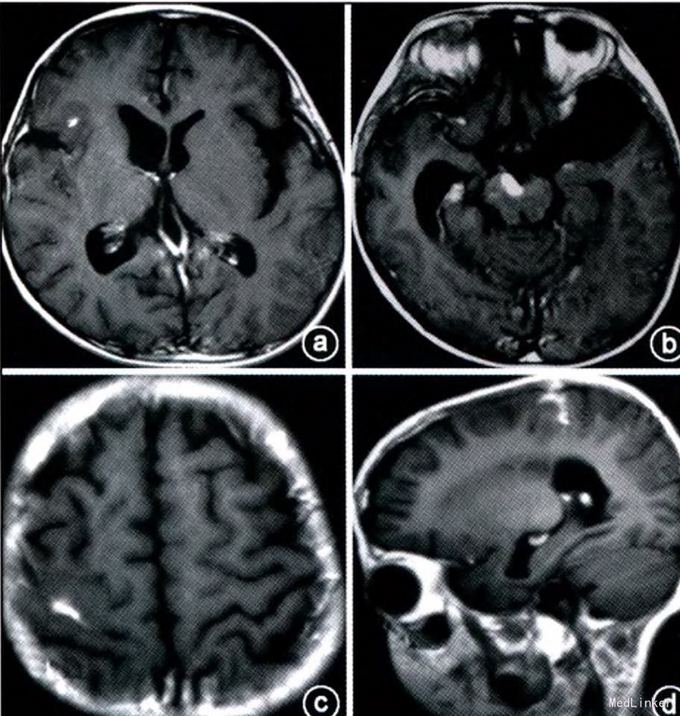

辅查:眼底检查示双侧乳头水肿,颅脑CT示右额叶等密度占位,伴钙化。增强后明显强化,约2厘米。增强MRI T1加权呈等信号,T2 加权等或稍低信号。脑桥、右顶叶也可见病灶,病灶周围可见水肿。

初步诊断:颅内感染性肉芽肿:淋巴瘤?结核?白血病脑病? 处理:考虑患儿有明显颅内压增高症状,行右侧扩大翼点入路开颅手术,切除右额叶明显病变。病理示明显新生血管形成和炎性细胞浸润,部分见组织细胞,核为肾形,疑为朗格汉斯细胞。免疫组化CD68及波形蛋白阳性。S-100及Cd 1a部分细胞阳性。 确诊:颅内朗格汉斯增生症。